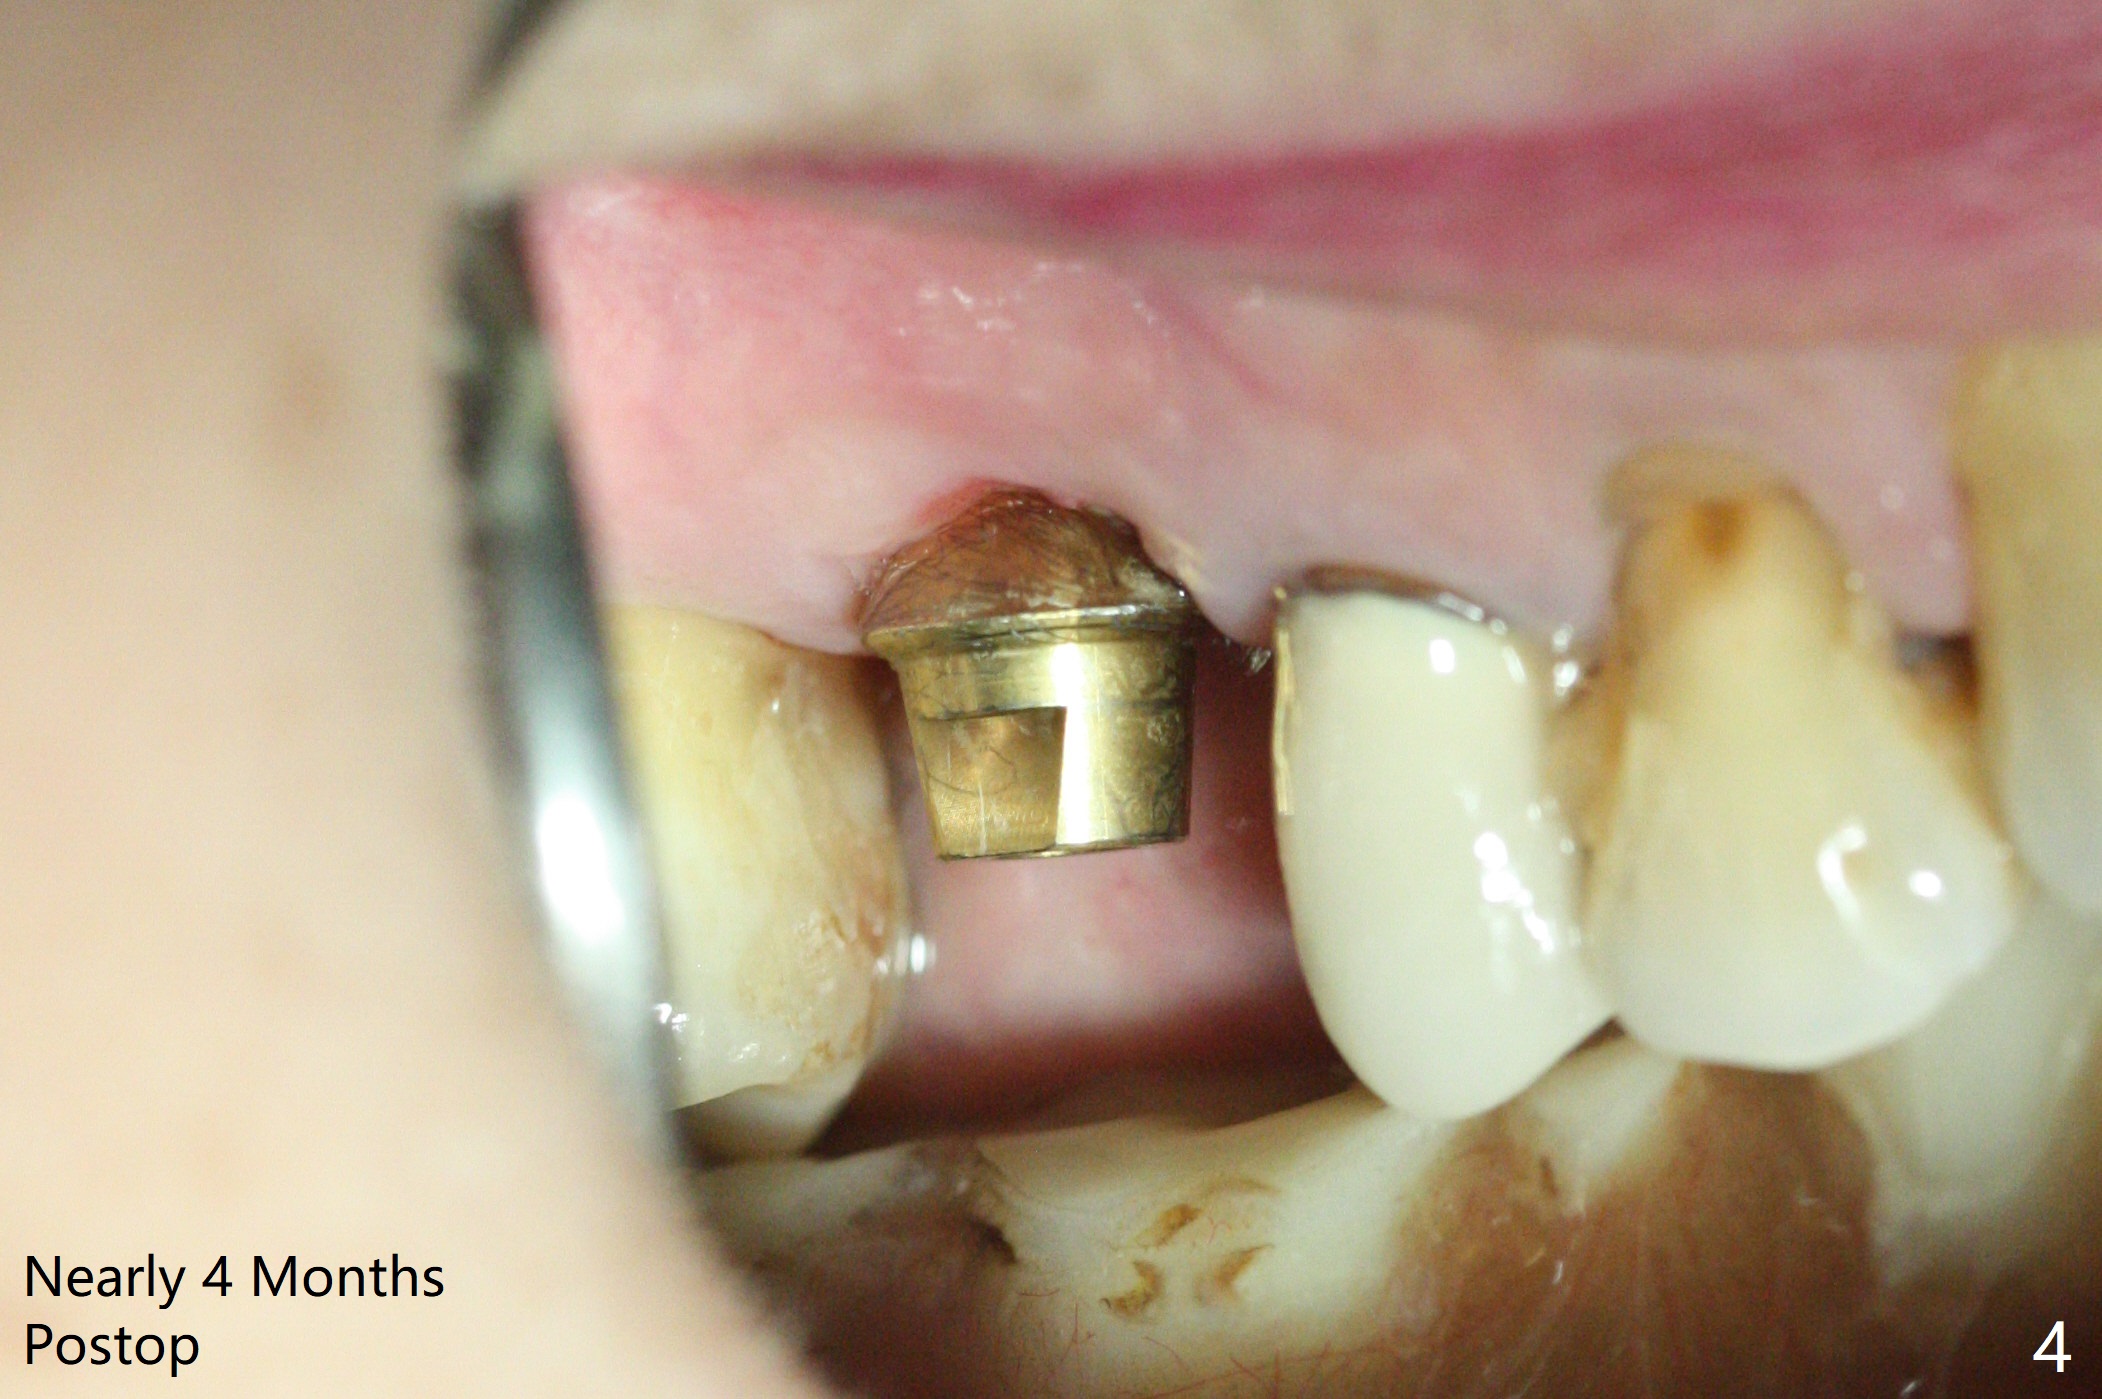

A 5x10 mm implant is placed at #3 according to drill sequence except 4.5x10 mm drill having to be used (plan: underdrilling using 4.0x10 mm as the last one) because of dense bone. Insertion torque is >50 Ncm. Although the implant apparently penetrates the sinus floor (Fig.1), the bottom of the osteotomy is intact before implant placement. In addition, the 12 mm bone trimmer does not touch the septal bone, while 2.2x8.5 mm drill starting to remove bone. In spite of using the largest cementation abutment (6.5 mm), the buccal (Fig.2) and palatal sockets with bone graft (*) are exposed. An immediate provisional (Fig.3 P) is fabricated for remaining socket closure. The buccal gingiva appears to have receded relative to the abutment margin nearly 4 months postop (Fig.4). The mesial crestal bone defect seems to be repairing (Fig.5 (*),6). The abutment later changes to a 5.7x5.5(2) mm one with margin modification buccomesiolingually before impression.